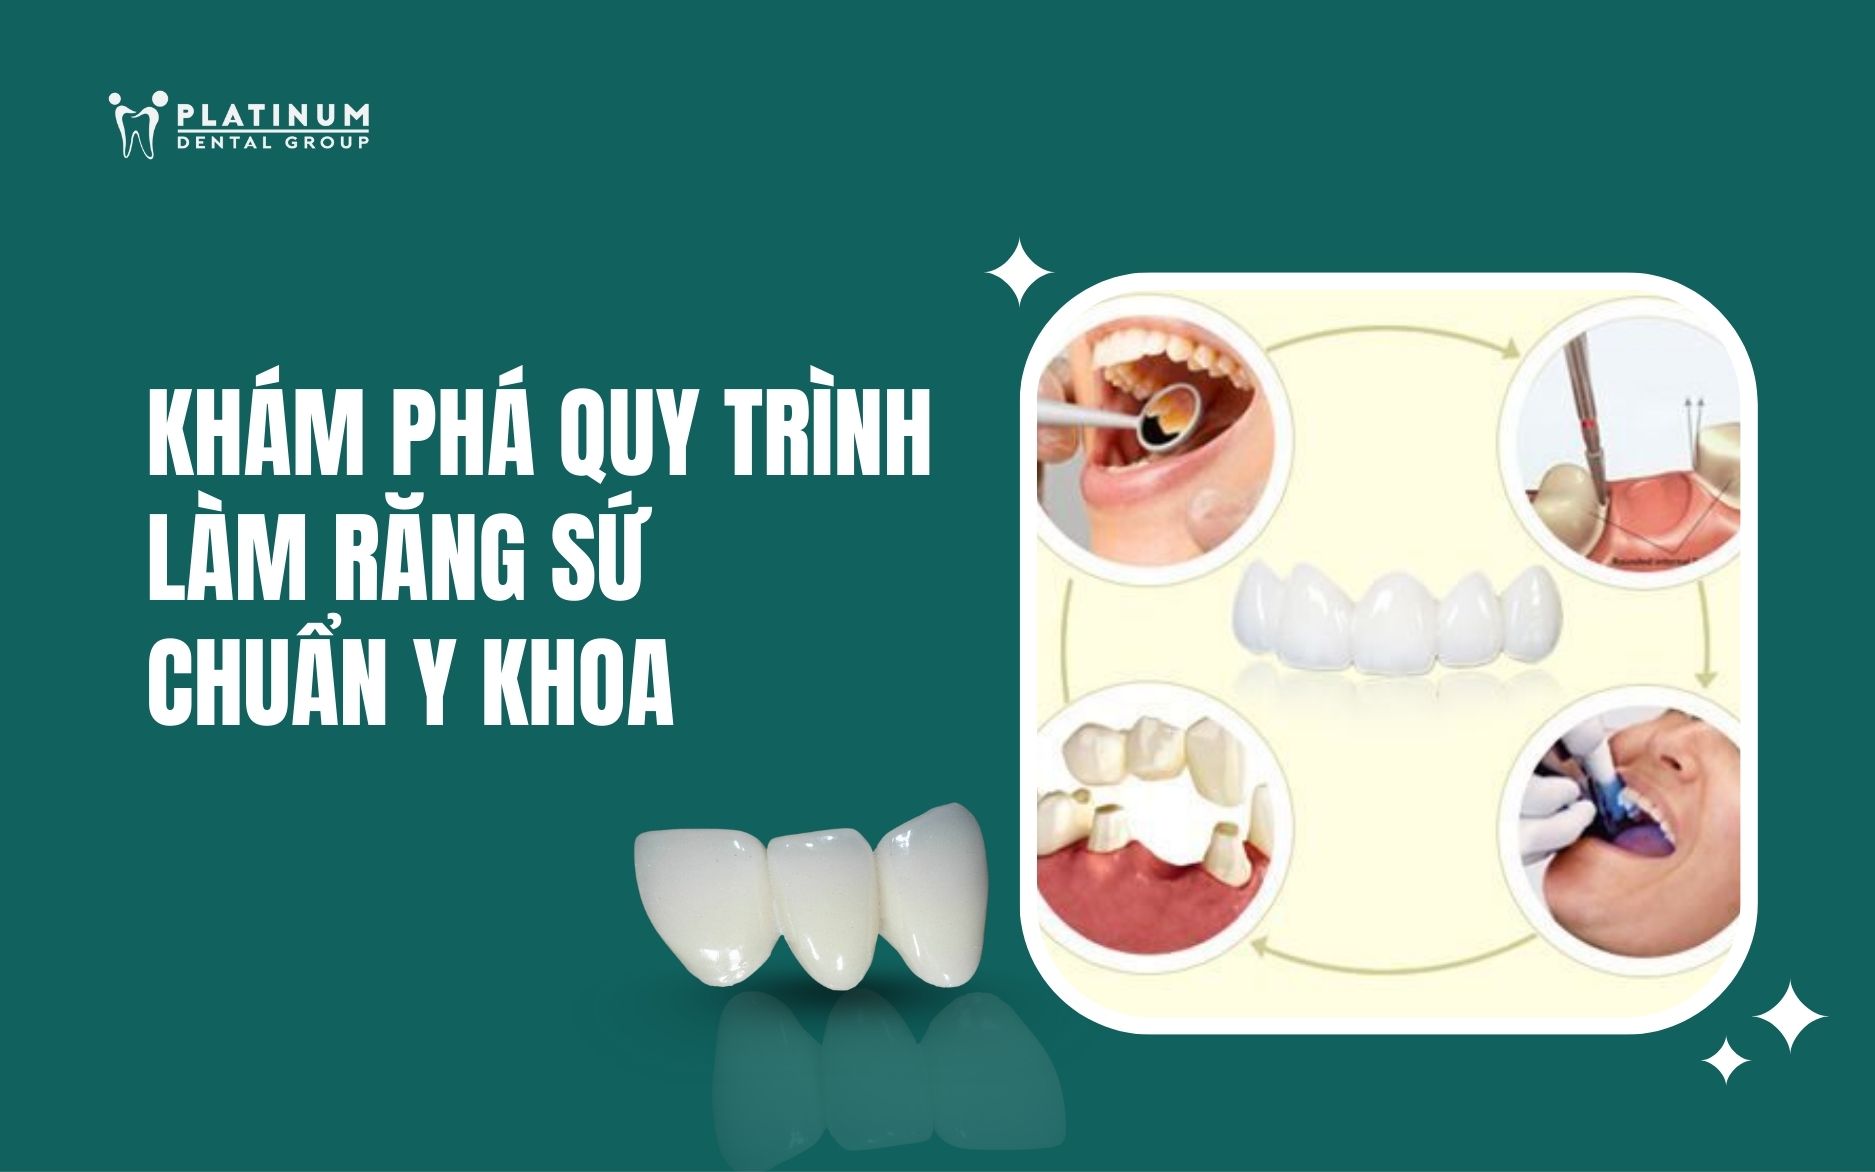

Trang tin cập nhật kiến thức nha khoa toàn diện từ chăm sóc răng miệng hằng ngày, phòng ngừa bệnh lý đến cập nhật công nghệ điều trị hiện đại. Tất cả nội dung đều được biên soạn và chọn lọc từ đội ngũ bác sĩ giàu kinh nghiệm tại Platinum Dental.